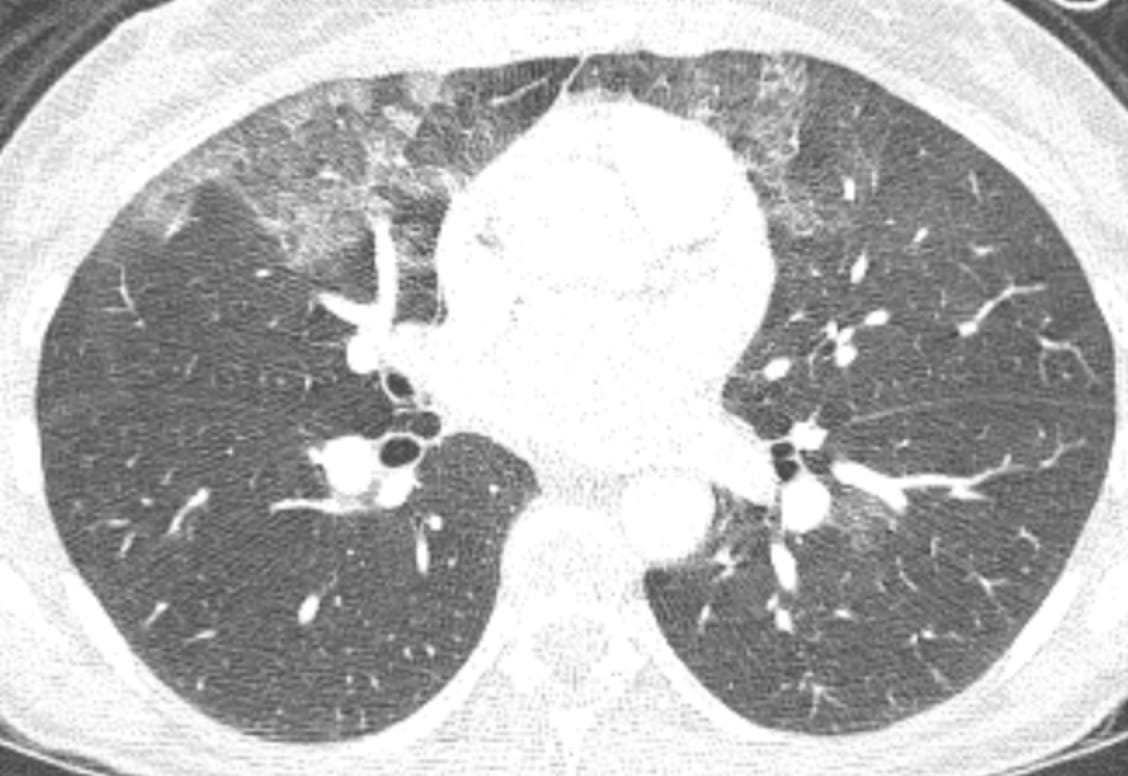

CT of Acute Lung Injury Edema

Don’t confuse the posterior lung opacities with anything else other than consolidated and —particularly—atelectatic lung. This is potentially so-called recruitable (by different ventilatory strategies) lung.

The concepts of (dorsal) “sponge” and (ventral) “baby” lungs are evocative. The size of the ventral aerated lung in ARDS (with the patient supine) suggests a “baby” lung— as conceptualized by Gattinoni et. al.